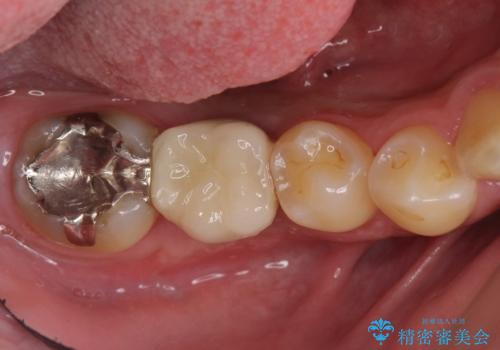

インプラントの術式は比較的単純で、難しくないですが、予後を見据えて角化歯肉を増やす手間をかけることが大変重要です。

長期的な予後を見据えた治療をしてもらえる病院を、慎重に選んでいただくことをお勧めします。

- 52万円 内訳:ストローマンインプラント(1本)42万円(仮歯、ジルコニアクラウン、カスタムアバットメント含む) 静脈麻酔 5万円x2回費用は治療当時の料金となります